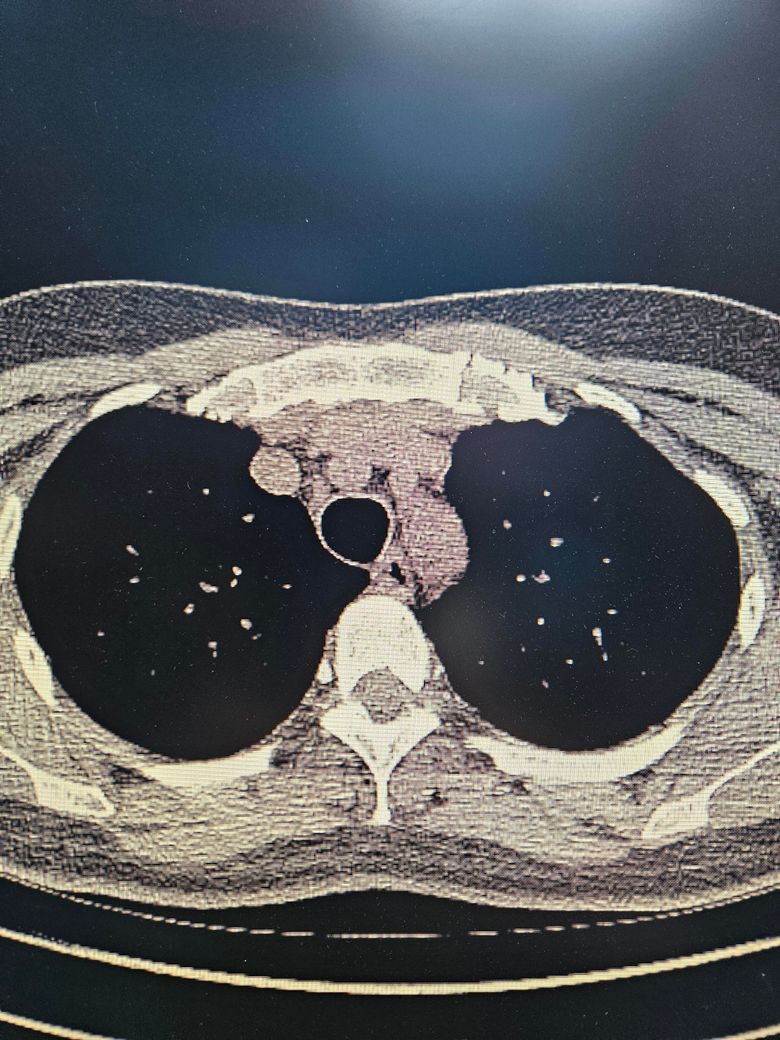

결핵의심 ct 사진인데 정확한건가요

결핵의심같다고 ct검사했는데 결핵이맞을까요..

객담검사했는데 배양검사결과는 아직안나오고

도말검사 pcr 다 음성나왔어요 ㅜ

• 2번 째 사진

올리신 CT 사진 두 장을 놓고 결핵 여부를 판단할 수 없으며, 심지어 올리신 CT 사진들을 폐를 자세히 볼 수 있는 세팅으로 설정되어 있지도 않습니다. 결핵의 경우에 CT 검사에서 의심할 수 있는 여러가지 소견들이 있을 수 있긴 하지만 확진을 내리기 위해서는 추가적인 검사들이 필요합니다. 일단 도말검사, PCR 검사에서 음성이 나왔다면 다행이며 결핵이 아닐 가능성이 충분히 있어 보입니다.